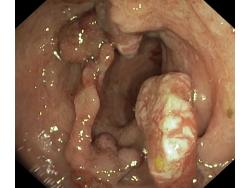

Nowotwory przewodu pokarmowego

Polipowatość

Polipy